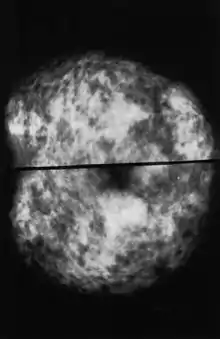

Normal (left) versus cancerous (right) mammography image.